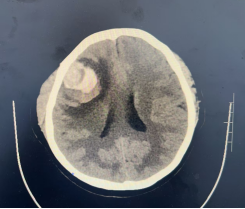

到院行头CT、MRI检查后初步诊断为颅内占位性病变,但因其影像学表现非常复杂,不同于常见颅内肿瘤,吴镝主任所带领的治疗团队联合北京天坛医院等的数位专家对此病例进行充分的分析讨论,肿瘤性质考虑为颅内黑色素瘤,肿瘤位于重要功能区、边界不清晰、血运极其丰富,手术难度很大,最终通过充分论证制订了通过精准入路、显微精细操作、术中严密监测等预案,力争把手术风险降到最低,为后续综合治疗创造条件。

术前